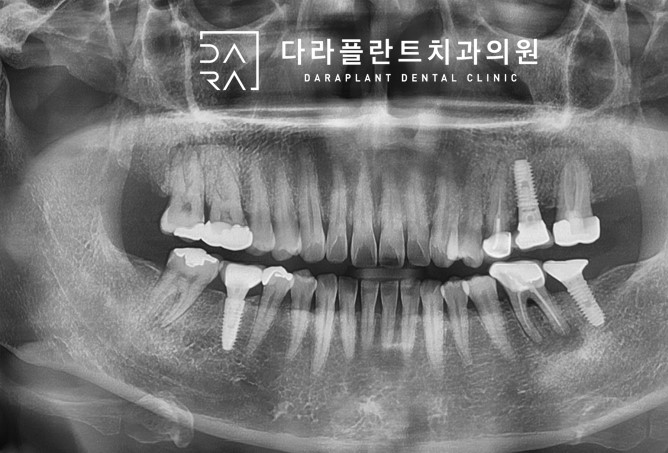

행신동 신경치료 치과. 뿌리 끝에 염증이 생겨서 신경치료를 한 케이스 치유 상태.

안녕하세요 행신동 신경치료치과 다라플란트입니다. 오늘은 뿌리쪽에 염증이 생겨서 신경치료를 치아가 어...